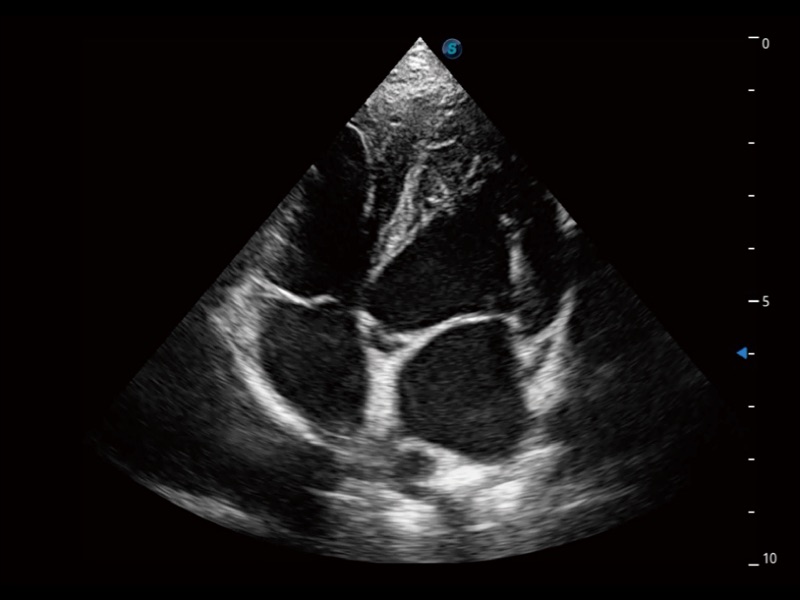

(犬)四腔心

(犬)胎儿主动脉弓立体血流